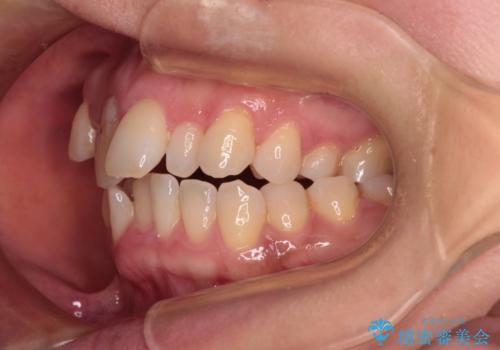

- 前歯のデコボコと咬み合わせの悪さを気にして来院された患者様です。

下顎骨が左側にズレて成長してしまったため、左側の咬み合わせが上下反対になっている状態でした。

そこまでの処置は望んでいらっしゃらなかったため、歯列矯正でのカムフラージュにより咬み合わせを改善することとしました。

予想通り左側の咬み合わせの調整に苦労をしましたが、最終的には違和感のない咬み合わせを達成することができました。